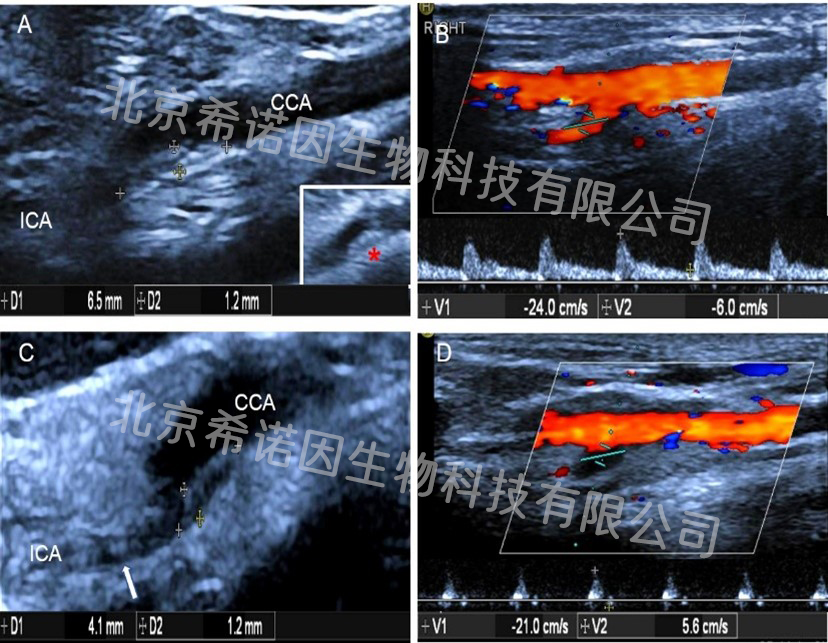

Vascular ultrasound examination was performed at nearly 2 years of the F0 generation. The results showed that 6.5×1.2mmechoic flat plaque was detected in the posterior wall of the initial segment of the right internal carotid artery in ApoE gene edits dogs (FIG. A), and the flow rate was 24/6cm/s (FIG. B), and the flow rate of the internal carotid artery was 20/6cm/s. 4.1×1.2mm plaque was detected in the posterior wall of the initial segment of the left internal carotid artery (FIG. C), and the flow rate was 21/6cm/s, presenting an "oscillating" flow spectrum (FIG. D). The flow rate of the internal carotid artery was 11/6cm/s, presenting an "oscillating" flow spectrum. Echoic flat plaques of 19.9x1.3mm were detected on the posterior wall of abdominal aorta, plaques of different sizes were detected in renal artery, iliac artery and superficial femoral artery, and vessels of different degrees of stenosis were detected.

Internal carotid atherosclerosis (pictures unpublished)